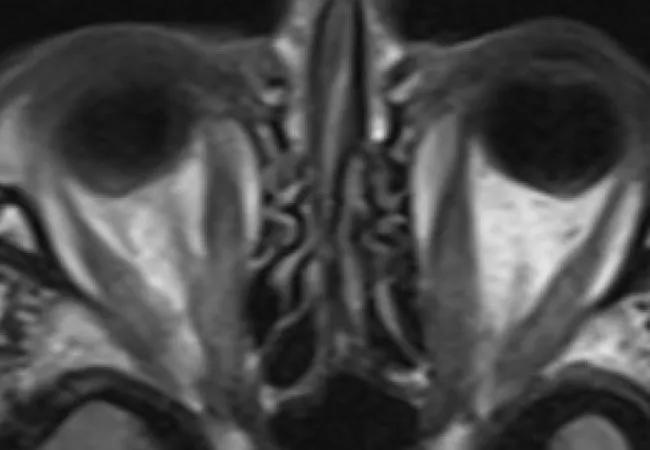

An MRI confirmed compression of nerves at the patient’s orbital apex. Since previous steroid treatment had not been effective at easing the compression, orbital decompression surgery was recommended.

MRI before teprotumumab (A,B) and after fifth infusion (C,D).